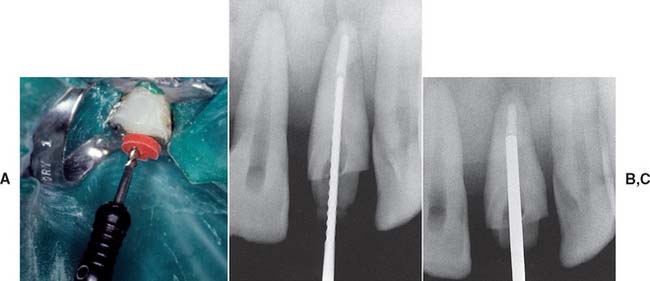

There are two commonly used methods to remove gutta-percha (Fig. 12-23): (1) using a warmed endodontic plugger, and (2) using a rotary instrument, sometimes in conjunction with chemical agents. Although more time consuming, the warmed endodontic plugger is preferred because it eliminates the possibility that the rotary instrument will inadvertently damage the dentin. If it is more convenient, the gutta-percha can be removed with a warmed condenser immediately after obturation. This does not disturb the apical seal.55,56 This method offers the additional advantage of allowing the operator to work in an area where the root canal anatomy is still familiar.

Fig. 12-23 Gutta-percha can be removed from the canal with a heated endodontic plugger. (A and B), a non–end-cutting bur (C) (e.g., a Gates Glidden drill). A ParaPost drill (D) can be used to parallel the post space wall (with a rubber stop to ensure accuracy of the preparation depth).

(A and B, Courtesy of Dr. D. A. Miller.)